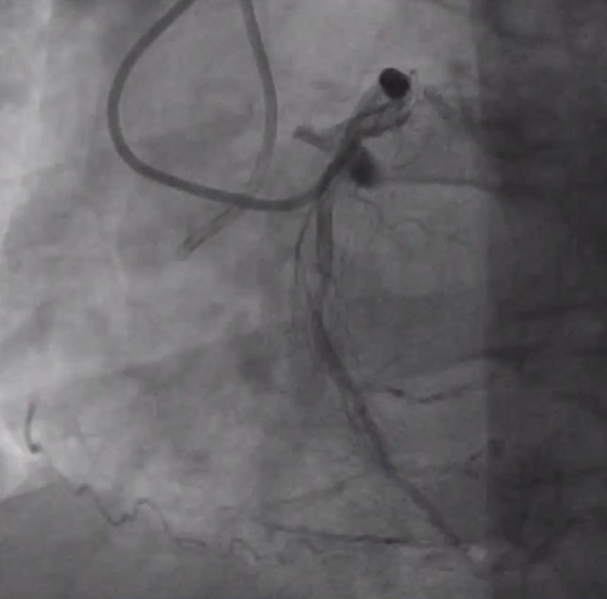

山西省心血管病医院暴清波教授结合病例分享了小球囊在高阻病变中的应用。首先是一例60岁的ACS病例,既往有RCA支架植入病史,本次入院冠脉造影提示RCA自近段闭塞。手术过程中,先后使用Filder XT-A导丝、Gaia 2导丝,成功通过闭塞段,但mini trek小球囊及Goodman小球囊均无法通过,闭塞段阻力较高,最终通过Firefighter™球囊锚定技术将球囊送入闭塞段以远。

RCA CTO病变

RCA支架植入后

西安交通大学第一附属医院郭宁教授认为对于这种高阻力的CTO病变,球囊锚定技术及小球囊掘进技术对于开辟管腔通道有重要价值,尤其是导丝在闭塞段走行不明确时,结合个人应用体会而言,使用Firefighter™球囊一点点跟进,可以达到“滴水穿石”、逐步撬开坚硬病变的效果。